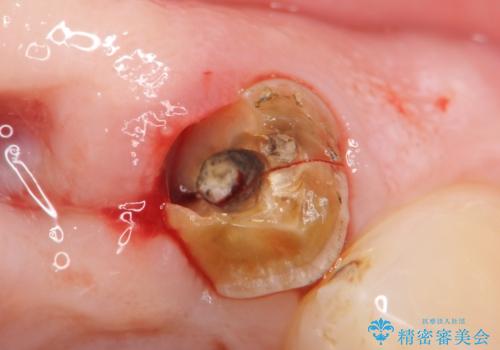

精査したところ、左上の側切歯(左上2)も破折しており保存不可能な状態でした。

左上の側切歯(左上2)を抜去し、右上の側切歯(右上2)の再根管治療後、セラミックのブリッジによる補綴を行いました。